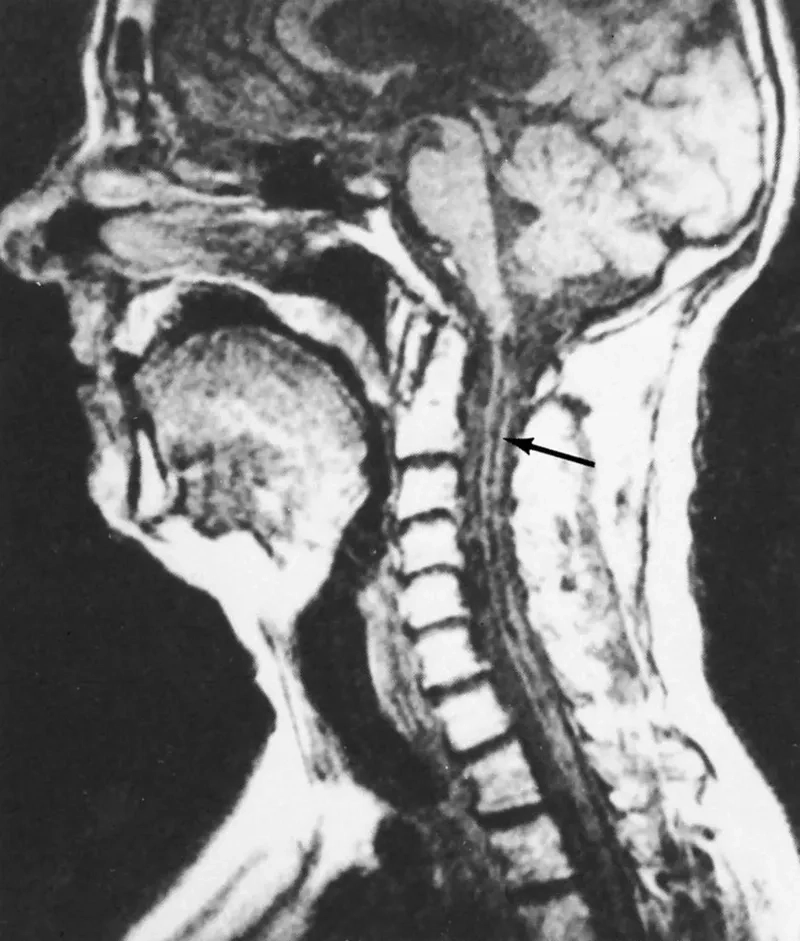

A before-and-after MRI following syringomyelia treatment